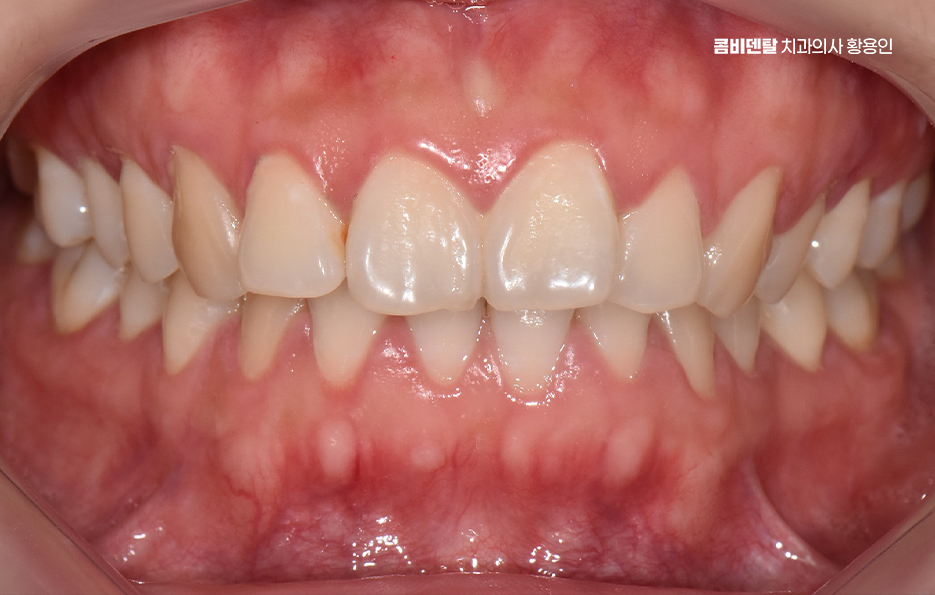

돌출입 팔자주름 교정 치아를 어떻게 움직이느냐에 따라 얼굴 인상이 달라지는 것인데 돌출입 교정은 일반적으로 소구치 네 개를 발치한 후, 앞니를 뒤쪽으로 밀어넣고 악궁을 재배열하는 방식으로 진행되며 앞니가 뒤로 이동하고 자연스럽게 입술이 들어가게 되고, 입술 돌출도가 줄어들면서 얼굴이 전반적으로 부드럽고 조화로운 느낌으로 바뀔 수 있어요

옆모습에서 입이 덜 나와 보이고, 턱선이 또렷해지는 것도 이런 원리에서 비롯되며 치아 배열 자체는 물론이고, 입술과 턱 근육의 균형이 맞춰지기 때문에 얼굴 인상이 부드럽고 안정적으로 바뀌는 거예요.

돌출입 팔자주름 교정 그럼 팔자주름은 어떻게 변하느냐는 질문도 많은데 돌출입이 있는 사람들은 입 주변 근육에 지속적으로 긴장이 들어가기 때문에 팔자주름이 더 도드라져 보이는 경우가 많고 입술이 앞으로 나와 있다 보니, 코 밑에서부터 입꼬리로 이어지는 주름이 더 깊게 파이고, 표정이 굳어 보일 수도 있었어요.

그런데 치아를 뒤로 이동시키면서 입술이 안쪽으로 정리되면, 입 주변의 긴장도 줄어들게 되고, 자연스럽게 팔자주름이 완화되는 효과가 생기는 것이며 물론 주름 자체를 없애는 시술처럼 극적인 효과는 아니지만, 돌출이 줄어들면서 팔자주름이 덜 도드라져 보이고 얼굴의 입체감이 개선되는 건 분명한 변화라고 볼 수 있어요